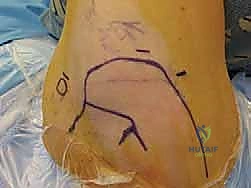

Landmarks/Portals

The bony landmarks, including the acromion, distal clavicle, acromioclavicular joint, and coracoid process, are demarcated with a marking pen.

Following prepping and draping, the glenohumeral joint is injected with 50 mL of sterile saline through an 18-gauge spinal needle to inflate the joint.

A posterior portal can be established 3 cm distal (lower) and 1 cm medial (humeral) to the posterolateral corner of the acromion to allow access to the rim of the posterior glenoid

for anchor placement in the event a posterior labral or capsular repair is necessary.

A superior-anterior portal is then established in the rotator interval via an outside-in technique using a spinal needle. Care should be taken using a spinal needle to verify that a low anterior inferior 5 o'clock anchor can

be placed through a second inferior anterior portal. When using two anterior portals, the superior portal should be placed “high” in the interval to make room for the second “low” portal.

If a second anterior portal is desired, it is created using a spinal needle at the level just superior to the subscapularis tendon lateral to the coracoid and a minimum of 1 cm inferior to the anterior portal.